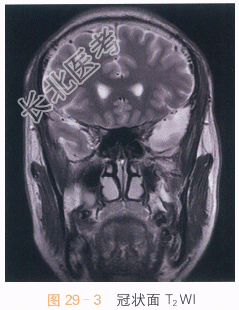

影像学资料如图29-1~图29-4所示。

读片分析:头颅横断面T₁WI、T₂WI见左侧中颅窝异常信号灶,呈长T₁WI、长T₂WI信号,边界清晰,左侧颞极受压,信号无明显异常改变;冠状面T₂WI及矢状面T₁WI亦可见左侧中颅窝长T₁WI、长T₂WI信号影,左侧颞极受压改变。结合患者病史,诊断为蛛网膜囊肿。